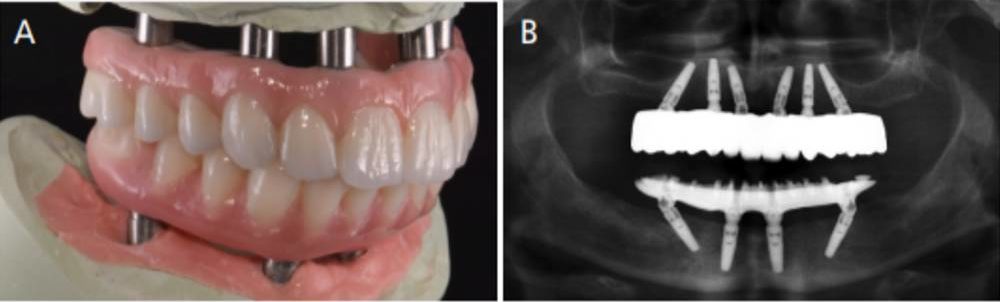

Fixed Hybrid Implant Denture. Our smile design implant dentists will design treatment with the minimal number of implants that is right for you. A hybrid denture is attached by four or more implants in the jaw, depending on the jawbone size and shape. What are fixed implant dentures? Learn which is the best replacement my mom chose the less expensive denture implants to my surprise. She had the budget for a full fixed bridge, which cost almost twice as much at $11,000. Sometimes called locator over dentures. A lower hybrid denture can be fixed on as few as four dental implants. Fixed hybrid bridge, all on 4 dental implants, and zirconia fixed bridge. An upper denture can be fixed on as few as six dental implants. Just like regular dentures whether you choose dentures, dental implants, or hybrid implant dentures, you'll need to keep your new teeth clean and in good condition. There are a lot of dental procedures to fix this type of dentures the most common are: Fixed bridge has 3 subtypes: Regular hybrid dentures, all on 4, snap on dentures. As the name implies, hybrid implant dentures consist of dentures that are fixed onto implants. A hybrid denture prosthesis is the.

A Step By Step Guide To Converting Denture To Interim Hybrid Prosthesis Spear Education. Regular hybrid dentures, all on 4, snap on dentures. Just like regular dentures whether you choose dentures, dental implants, or hybrid implant dentures, you'll need to keep your new teeth clean and in good condition. What are fixed implant dentures? There are a lot of dental procedures to fix this type of dentures the most common are: Fixed hybrid bridge, all on 4 dental implants, and zirconia fixed bridge. A hybrid denture is attached by four or more implants in the jaw, depending on the jawbone size and shape. An upper denture can be fixed on as few as six dental implants. Fixed bridge has 3 subtypes: Sometimes called locator over dentures. As the name implies, hybrid implant dentures consist of dentures that are fixed onto implants. She had the budget for a full fixed bridge, which cost almost twice as much at $11,000. Our smile design implant dentists will design treatment with the minimal number of implants that is right for you. Learn which is the best replacement my mom chose the less expensive denture implants to my surprise. A hybrid denture prosthesis is the. A lower hybrid denture can be fixed on as few as four dental implants.

A lower hybrid denture can be fixed on as few as four dental implants. This entry level job will train you to be part of a trade you may never have known exist. E patient cannot remove and are either screwed directly on the implant or connected via abutments. Unlike dentures that have pink acrylic and plastic teeth, fixed bridges are porcelain fused to metal or monolithic zirconia such as the prettau dental implant bridge. On the up side, these failures prompted advancements in denture tooth materials specifically designed to cope with the additional. Hybrid dentures in 2019 have several material choices available now. Today with dental implants we are able to fabricate a fixed solution. What are fixed implant dentures? These implants provide the necessary stimulation for bone growth and health. Implant supported dentures are fixed, meaning they stay in at all times. A hybrid denture that she keeps in all the time and is very secure. How fixed hybrid implant restoration is done. A hybrid denture is attached by four or more implants in the jaw, depending on the jawbone size and shape. A hybrid denture prosthesis is the. Implant/abutment supported fixed (hybrid) dentures: There are a lot of dental procedures to fix this type of dentures the most common are: Immediate dentures are inserted on the same day the teeth have been extracted. Come see us for a great 😀. Just like regular dentures whether you choose dentures, dental implants, or hybrid implant dentures, you'll need to keep your new teeth clean and in good condition. Although the retention offered by an implant bar overdenture is far better than that offered by a traditional complete denture, the removable nature of the appliance may leave. Codes for fixed complete dentures are d6114 and d6115. The process for placing fixed dentures is basically the same if they are made to replace a complete set of upper teeth, lower teeth or both upper and lower teeth. A lower hybrid denture can be fixed on as few as four dental implants. Fixed implant supported dentures or fixed dentures or hybrid dentures. These include debonding, recurrent caries, gingivitis. An upper denture can be fixed on as few as six dental implants. Implant supported removable dentures or snap on dentures are a boon to patients who want an economical solution for loose dentures. Regular hybrid dentures, all on 4, snap on dentures. From fixed hybrid dentures to prettau full arch zirconia bridge. Sometimes called locator over dentures. Accurate fit and occlusion straight out of our lab helps to save your practice time and money.